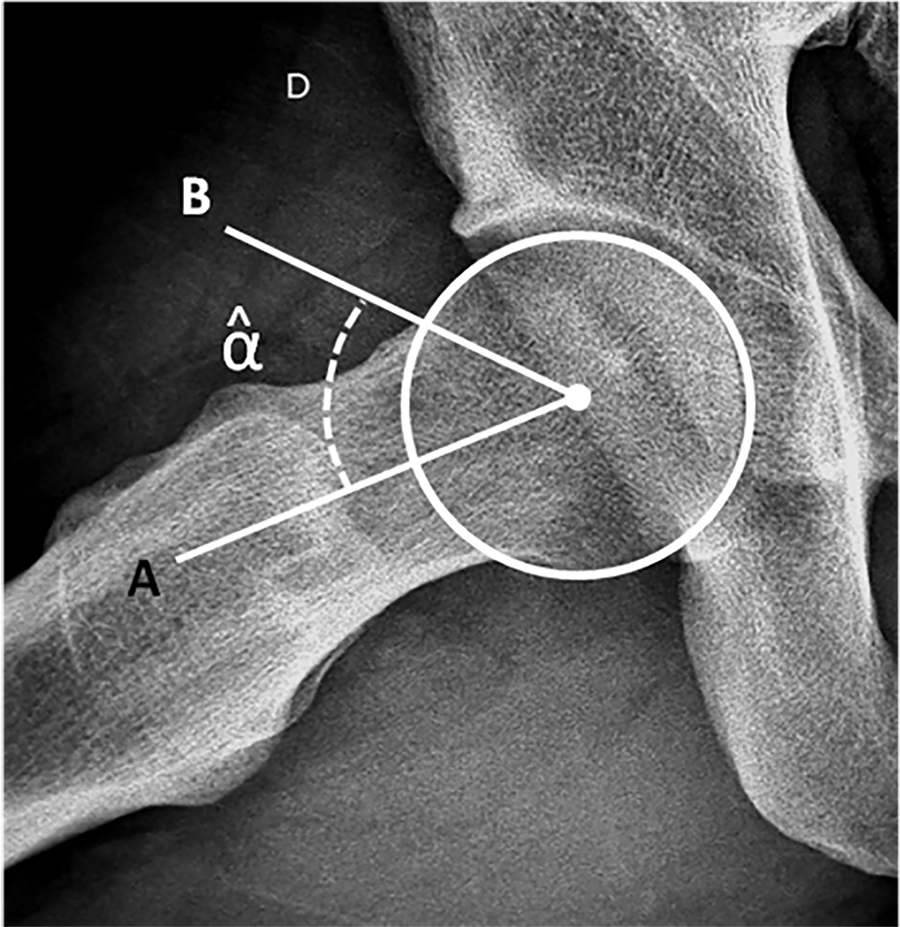

Prevalencia de Deformidades Tipo Cam de Cadera en Personas Asintomáticas

María Belén Orlowski, Gustavo Gómez Rodríguez, Jorge Chahla, Damián Arroquy, Jorge Guiñazú, Martín Carboni Bisso, Tomás Vilaseca

ARTÍCULO ORIGINAL